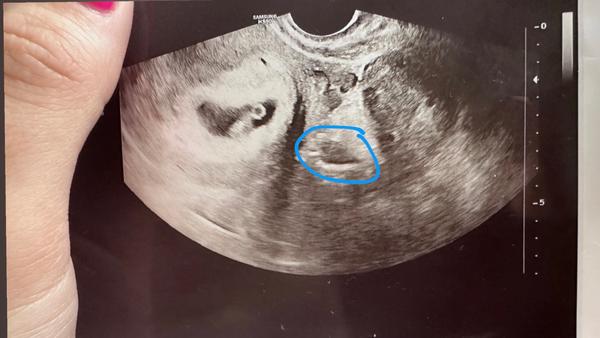

Co se nachází na ultrazvuku v modrém kroužku?

Ahoj, nevíte co to je na utz v modrém kroužku?

Ultravuk z kolikátého týdne to je? Pokud je to "velmi čerstvé" těhotenství, tak útvar, na který se ptáš, je mimo dělohu (a děloha je to v levé části - s viditelným žloutkovým váčkem a rostoucím miminkem vedle). Pokud je to pokročilé těhotentví někde kolem třetího trimestru, je to "řez" miminkem a je to tak rozmazané, že se opravdu nezorientuji.